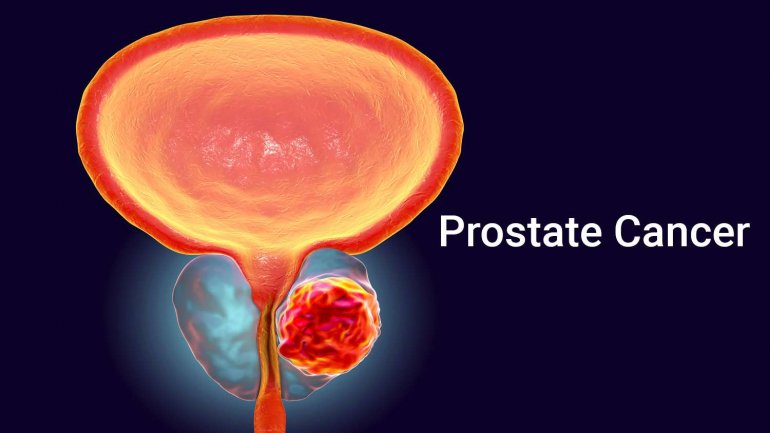

Αύξηση των διαγνώσεων καρκίνου προστάτη τα επόμενα χρόνια

Η αναμενόμενη αύξηση της επίπτωσης της νόσου απαιτεί αύξηση τόσο του εξειδικευμένου υγειονομικού προσωπικού που θα μπορεί να διαχειριστεί αυτούς τους ασθενείς όσο και των μέσων που απαιτούνται για τη διάγνωση και θεραπεία τους.